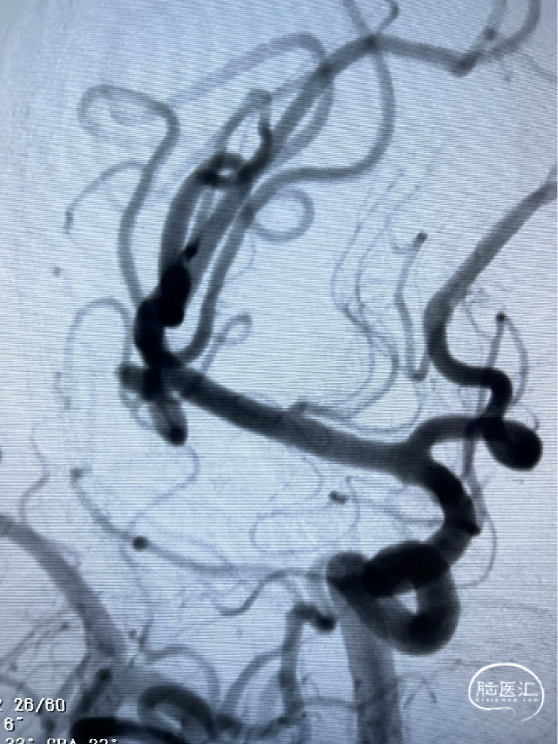

术前造影

CTA提示:右侧大脑中动脉动脉瘤。

造影提示:动脉瘤瘤颈累及上下干支,下干支与M1成角较锐S弯;患者右侧颈内动脉非常迂曲。

3D造影成像:动脉瘤大小约3.7*3.1mm。

其它颅内血管未见异常。